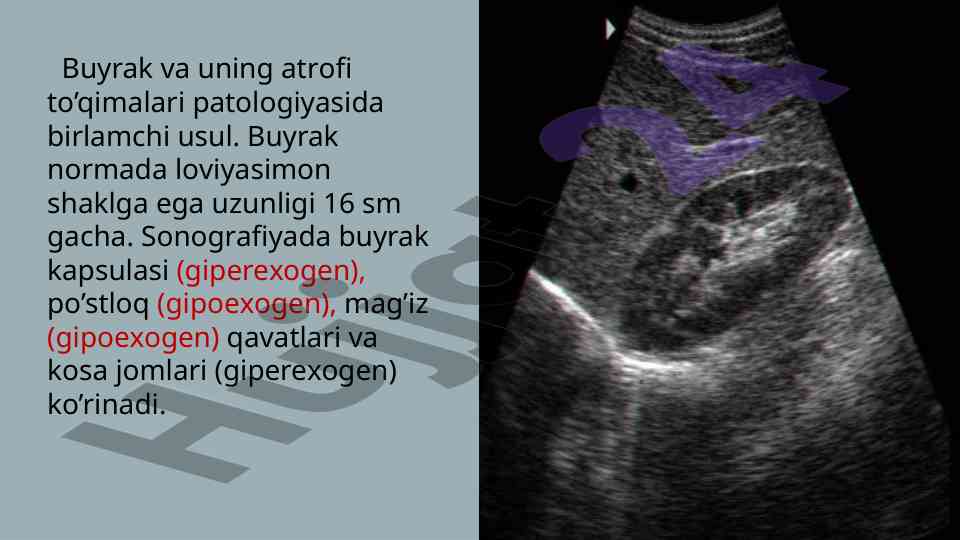

Ushbu maqola buyrak va siydik yo'llari nurli tekshirish usullarini, jumladan, sonografiya va ekskretor urografiyani, ularning afzalliklari va kamchiliklarini o'rganadi.